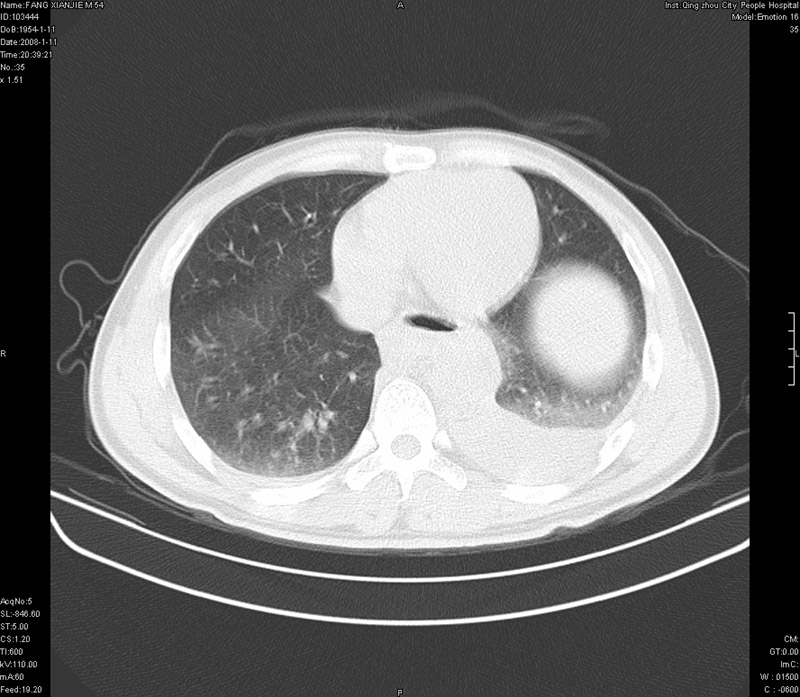

ct11308:胸部外伤1小时(证实病例) (2008-1-13 16:2)结果如下:病人入院后两小时后症状加重,8小时后在征得病人家属同意做了ct增强扫描。如下图。最终临床诊断:外伤性胸主动脉破裂并纵隔内血肿。由于有运动性伪影,胸骨在矢状面重建的图像似有骨折征,这是一种假象,我们称之为“假骨折”,这在多层ct重建中经常性遇到,必要时要结合横断图像鉴别之。现在,病人的一般情况较差,是否要手术家属尚有争议,如果手术修补,难度较大,需要专门预定制作固定支架。

当然,对于该病例,其它非重要的诊断还有:右侧少量气胸;左侧胸腔积液;左侧轻度肺挫裂伤。对于纵隔内血肿,我们曾经遇到过多例,也有怀疑主动脉的破裂,但是,均未得到具体出血部位的明确诊断。